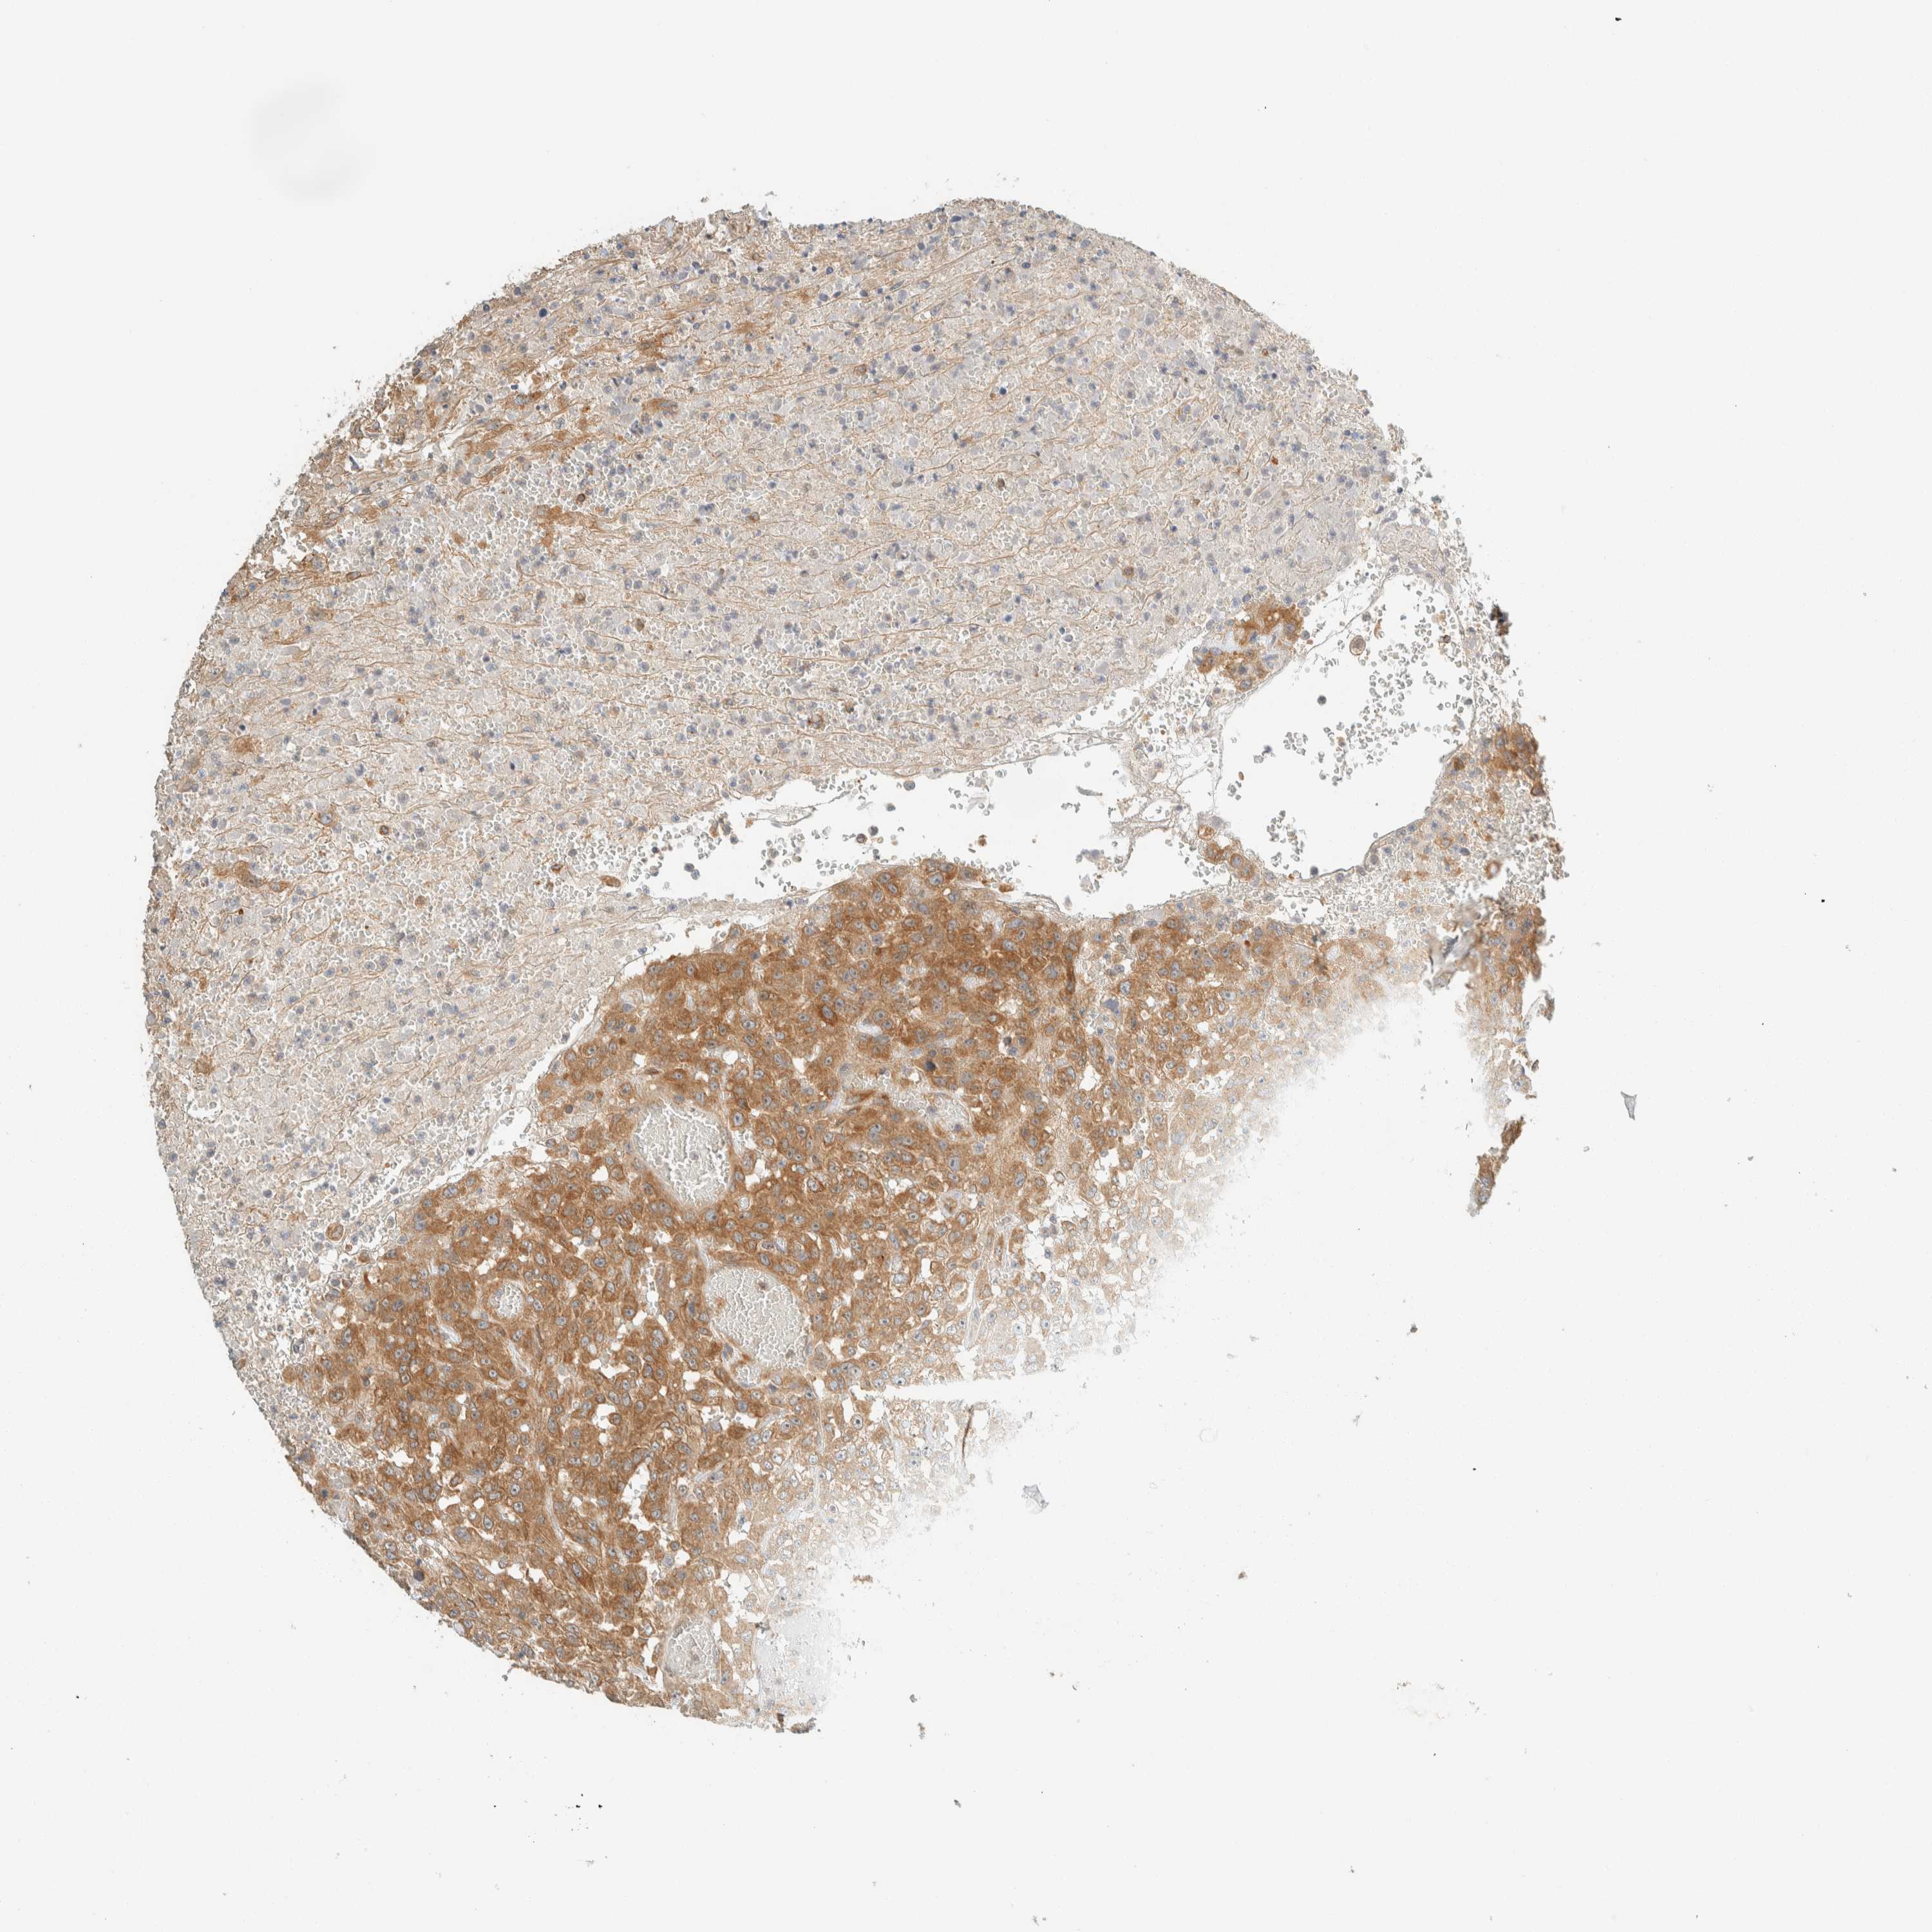

UROTHELIAL CANCER - Protein expressioni

A mouse-over function shows sample information and annotation data. Click on an image to view it in a full screen mode. Samples can be filtered based on level of antibody staining by selecting one or several of the following categories: high, medium, low and not detected. The assay and annotation is described here.

Antibody stainingi

Antibody staining in the annotated cell types in the current human tissue is reported as not detected, low, medium, or high, based on conventional immunohistochemistry profiling in selected tissues. This score is based on the combination of the staining intensity and fraction of stained cells.

Each image is clickable and will lead to virtual microscopy that enables deeper exploration of all samples and also displays staining intensity scores, fraction scores and subcellular localization as well as patient and tissue information for each sample.

Antibody HPA023399

Antibody HPA023822

Staining

High

Medium

Low

Not detected

Intensity

Strong

Moderate

Weak

Negative

Quantity

>75%

75%-25%

<25%

None

Location

Nuclear

Cytoplasmic/membranous

Cytoplasmic/membranous,nuclear

Urothelial carcinoma, Low grade

Urothelial carcinoma, High grade